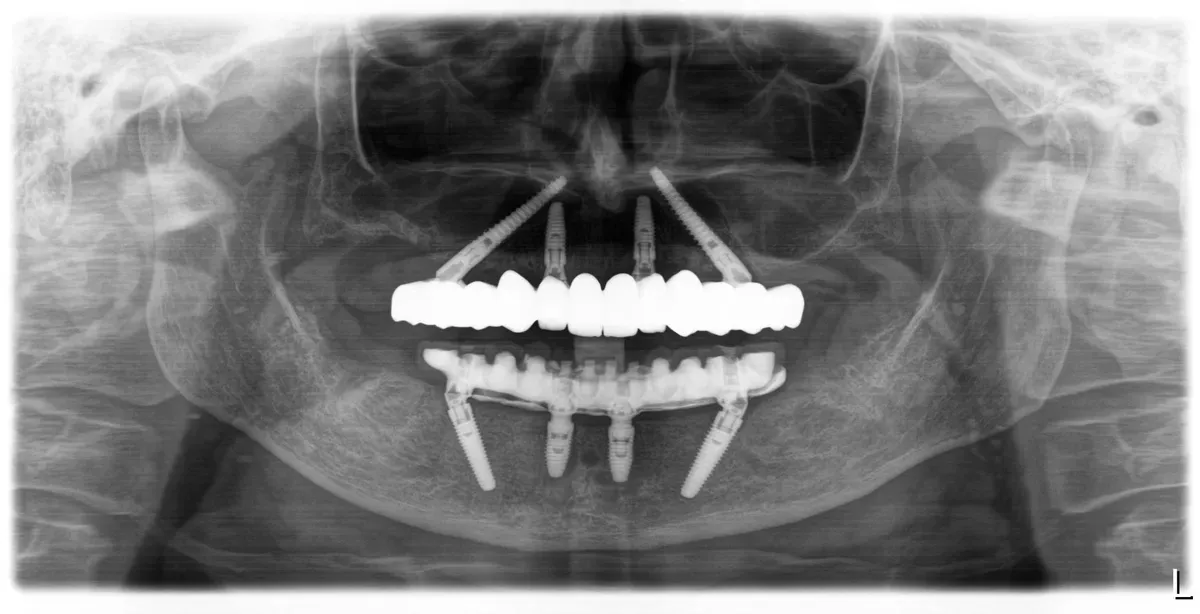

Pacijentica je došla u IMED zbog lošeg stanja u čeljusti, a nakon prvog pregleda preporučen joj je FP1 All-on-4 zahvat u gornjoj i donjoj čeljusti.

Zahvat je izveden u općoj anesteziji za maksimalnu udobnost i sigurnost pacijentice tijekom cijelog postupka, a nakon ugradnje implantata postavljen je trajni cirkonski rad bez umjetnog zubnog mesa u gornju čeljust, te metal-kompozitni rad u donju čeljust.

FP1 rješenje namijenjeno je pacijentima s dovoljno vlastite kosti u čeljusti te omogućuje iznimno prirodan izgled i vrhunsku funkcionalnost.